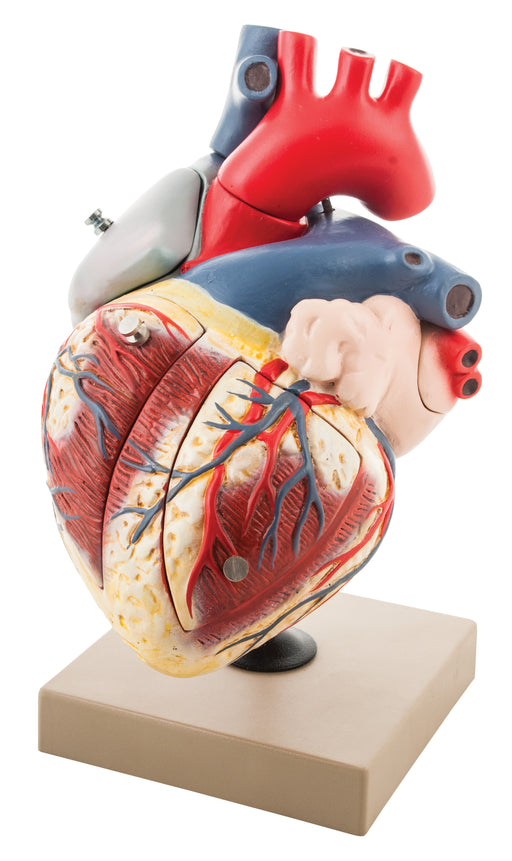

Human Heart Enlarged - 7 Parts

Enlarged 5 times. Sectioned so that both ventricles and atria open to expose the valves. Large blood vessels near the heart and musculature of the ...

View full detailsAM16035 -